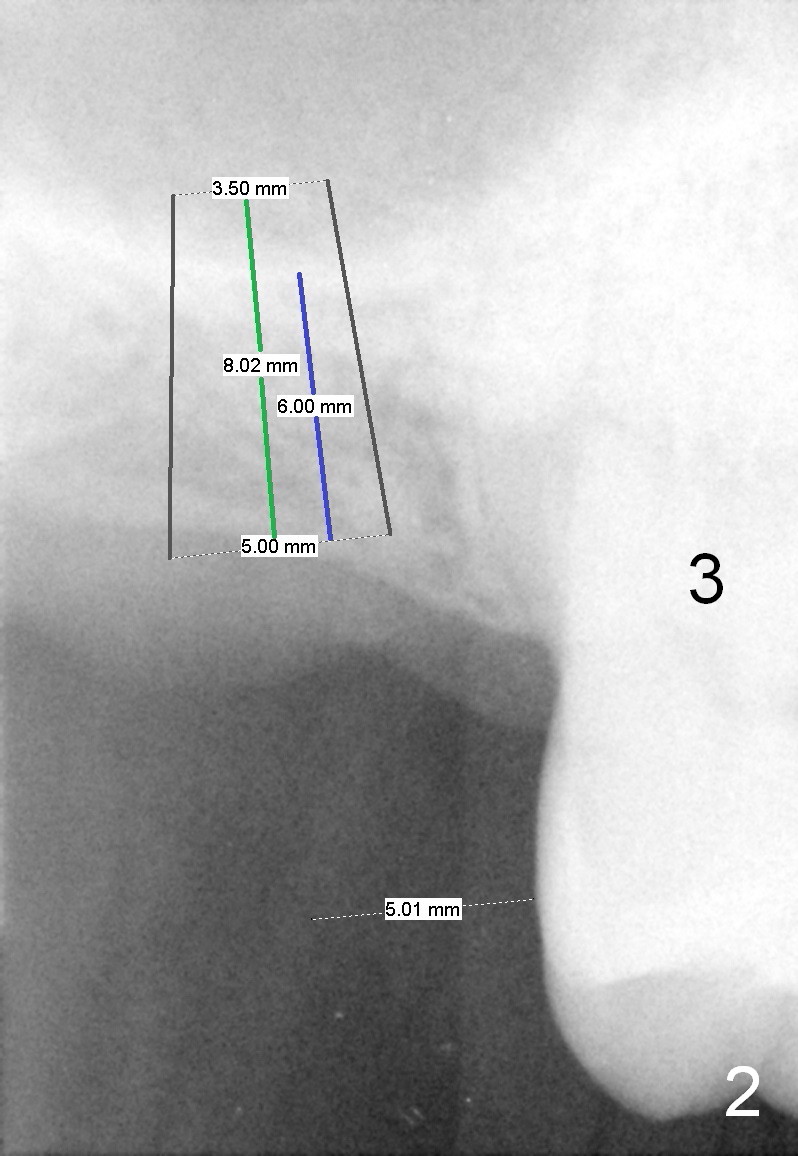

LJ will return for #2 implant placement 2 months post #31 implant placement. Fig.1 was taken 2 years ago. The tooth #2 had been supraerupted. The bone height is apparently 7.5 mm (blue line), but with proper manipulation, there would be 14 mm bone available (green line) for placement of an immediate implant. Fig.2 was taken a year post extraction. The bone height is reduced to 6 mm (blue line). With sinus lift, a 8 mm bone-level implant will be placed.

If the ridge is wide, use 4 mm tissue punch and 3 mm implant spacer (4/2+3=5mm) for access. Otherwise, an incision is made. Use a 2 mm pilot drill and 4 mm implant spacer to initiate osteotomy for 1-2 mm deep. Then use a 3 or 4 mm trephine for less than 6 mm deep. RT 2,3 or Bicon Osteotome (3.5 mm) will be used to lift the sinus floor. Prepare Metronidazole, allograft and Osteogen.